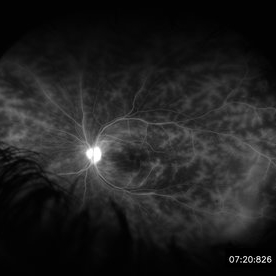

Retinal Vasculitis in Behcet's OS

Retinal Vasculitis in Behcet's OS

Jun 29 2018 by Gareth Lema, MD, PhD

IVFA at 7 minutes showing retinal vasculitis, cystoid macular edema, and disc staining.

Photographer: Ross Eye Institute, University at Buffalo Jacobs School of Medicine, Buffalo. NY

Imaging device: Optos

Condition/keywords: Behcet's Disease, cystoid macular edema (CME), disc staining, retinal vasculitis